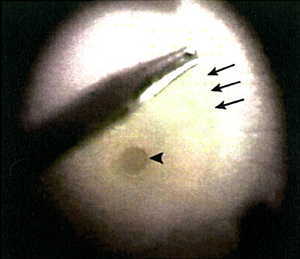

黃斑點穿孔是指黃斑點中央的凹位失去視覺神經組織,此情況大多由於老化或深近視所致。治療方法是施行扁平部玻璃狀體切除術,移除凹前表質玻璃體,並進行氣體和液體交換。大部份病人在手術後無須保持俯臥。患上黃斑穿孔的年長及深近視人士現時可以最新手術移除內界膜(圖1)治療,手術成功率超過90%。

![]() 圖1:手術期間的情況(從醫生的角度望向患者左眼):利用眼內手術夾,在已形成的黃斑點穿孔(箭頭所指位置)附近夾起內界膜(箭頭所在位置)。 |